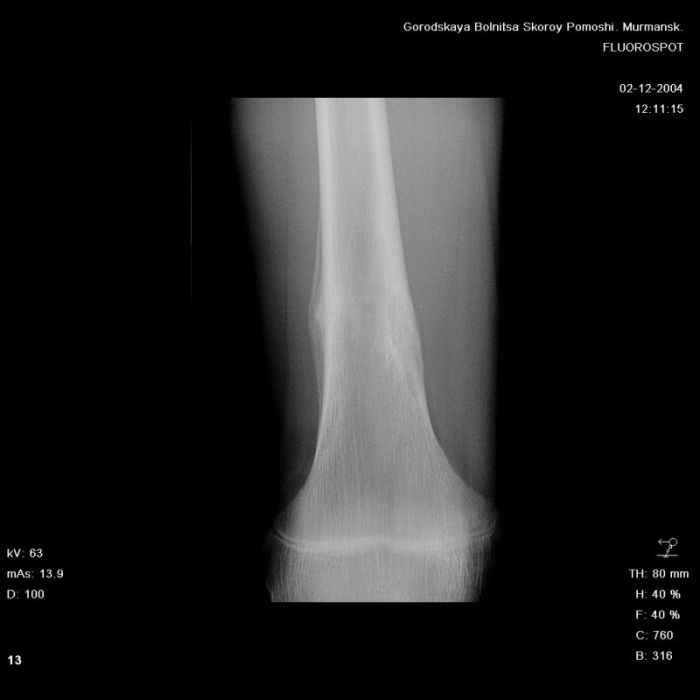

Здравствуйте, уважаемые коллеги!Представляю вашему вниманию интересный случай и пока что непонятный для меня в диагностическом плане. На днях в наше отделение (детской ортопедии и травматологии) поступил 13-летний мальчик по направлению из поликлиники с диагнозом: остеома нижней трети правого бедра.

Анамнез практически никакой: в следствие травмы (растяжение связок коленного сустава) от 07.11.2004 выполнены Rg-граммы в травмпункте и обнаружено опухолевидное образование. Первичные Rg-граммы я не публикую, так как они заметно худшего качества, да и динамики за прошедшие три недели не отражают. Болевой синдром купирован в течение трёх дней. В настоящий момент мальчика ничего не беспокоит. Ходьба не нарушена, опухоль пальпируется с трудом по задней поверхности в н\3 правого бедра, пальпация безболезненна, объем движений в суставах правой нижней конечности полный и симметричный. Кожа над опухолью не изменена.В нашей клинике проведено дополнительное обследование: общие анализы крови и мочи, биохимия крови без особенностей. Выполнены Rg-граммы на цифровом Siemens обычные и продольные томограммы срезами 3-5 мм, а также компьютерная томография поперечными срезами по 5 мм. Прошу обратить внимание, что на приведённых томограммах видны две полости 10х15 мм и 15х60 мм. Также имеются два опухолевидных образований наслаивающихся друг на друга: уплощённое и вытянутое 10х100 мм и элипсовидной формы 15х30 мм. Это хорошо заметно на фото a_1.jpg c_1.jpg и d_1.jpg. Плотность внутри полостей 125% от плотности костномозгового канала, плотность наружного опухолевидного образования 55% от плотности кортикального слоя. Также отмечается линия перелома по центру наружного опухолевидного образования.Исходя из полученных данных мнения в плане диагноза несколько разделились от 1)сочетания кортикальной фиброзной дисплазии и латентно протекавшего маршевого перелома н\3 правого бедра до 2)остеосаркомы. В отношении первого варианта не сходится отсутствие клиники при переломе такой крупной кости как бедро, второй вариант вообще оставлю без комментария, ибо некомпетентен. Хотелось бы услышать мнения коллег, с удовольствием ознакомлюсь с любыми предположениями и замечаниями.С уважением, Александр Е. КлоковОтделение детской ортопедии и травматологииБСМП г. Мурманска.

Думаю, что в этом случае можно думать и об остеоид-остеоме - достаточно чёткие края, более диафизарная локализация, наличие так называемого "гнезда" опухоли, и секвестра, а также отсутствие игольчатого периостита, козырька Кодмана, пятнистостого остеопороза, прорастания в костномозговой канал т.е. признаков остеогенной саркомы.